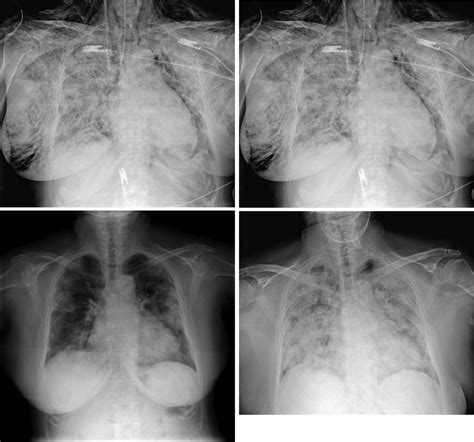

Debido a que los planos faciales son contiguos a los del cuello y del tórax, es posible la aparición de enfisema mediastínico, que resulta de la entrada de una gran cantidad de aire a los planos más profundos del cuello, pasando directamente a la parte superior y luego anterior del mediastino. La presencia de dolor tanto en el tórax como en la espalda, sugeriría la presencia de este tipo de enfisema, debiéndose tomar una radiografía de tórax para confirmar el diagnóstico.